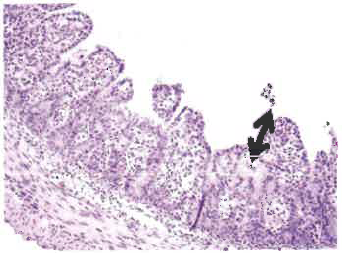

由于丁酸鹽對腸道健康有益,它可有效對抗豬流行腹瀉引起的不良反應 豬流行性腹瀉(PED)是由一種冠狀病毒引起的,該病毒與豬傳染性胃腸炎病毒具有一定相似性。 PED病毒首次于1971年在英國發現,后來大面積擴散到了多個歐洲、亞洲國家,造成流行性傳染。 圖1. PED的典型癥狀:仔豬嘔吐、腹瀉、消瘦 圖2. 急性病毒性腹瀉的典型癥狀:嚴重脫水、死亡 歐洲很少爆發高死亡率的嚴重疫情,但最近亞洲頻繁出現了有關疫情的報告。由于新毒株的出現,自2010年以來中國的爆發率大幅升高,美國直到2013年春才爆發疫情,這首次驗證了PED病毒的出現。 與此同時,加拿大也發現了該病毒,美國有27個州都發生了一例以上PED確診病例。近日,哥倫比亞和日本也可能出現了此病毒。 預防和治療 預防傳染的關鍵仍是確保良好的生物安全。但對于PED這樣的高傳染性疾病,維持生物安全并非易事。之前已經過病毒暴露并獲得免疫的母豬,可通過初乳將抗體傳給新生仔豬,使之在4-13日齡前獲得對經口感染病毒的免疫保護。目前,只有韓國、日本和中國有批準生產的PED疫苗。給經產母豬和后備母豬飼喂帶有病毒的小腸內容物或糞便也可激發免疫,但迄今為止,此種免疫不能持續長久,仍有復發的風險。此外,根據地方立法,使用此方法可能會觸犯法律,因為傳播污染物可導致疾病進一步擴散。 圖3. 正常新生仔豬的小腸絨毛腸絨毛(黑色箭頭處)較長,具有很大的表面積,以便吸收營養和水分。隱窩(黑色圓圈處)中有新細胞產生。 目前,治療方法主要為輔助性對癥治療:預防脫水(補充電解質,保持體溫),防止繼發性感染。 丁酸鹽的潛在用途 除以上治療方法外,業界還在尋求其他防治手段,以增強動物免疫抵抗力,促進豬的迅速痊愈。丁酸鹽對于腸道細胞生長以及腸道健康具有特殊功效,是一種不錯的選擇。研究表明,丁酸鹽不僅可為上皮細胞系統提供能量,而且能顯著促進小腸上皮細胞增殖、分化及成熟,還可改善結腸的屏障功能。 丁酸鹽可影響基因表達和蛋白合成,從而加速腸粘膜的發育、成熟和損傷修復。丁酸鹽的保護和修復作用已通過活體微生物攻毒試驗證實(以大腸桿菌感染仔豬,產氣莢膜梭菌感染家禽,導致細菌像PED病毒一樣破壞腸道屏障)。在攻毒試驗中,飼喂丁酸鹽能顯著減輕了PED對腸道的不良影響,使受感染的動物的生長率水平接近于受感染的動物。此外,丁酸鹽可調節離子吸收,有助于緩解腹瀉。 大量文獻以及養殖經驗均顯示,丁酸鹽對幼仔腸道發育的作用尤其顯著。研究表明,丁酸鹽可改善新生仔豬和斷奶仔豬的生長性能,給仔豬越早飼喂丁酸鹽,效果越好。這一特性對易受PED疾病威脅的幼崽非常有幫助。 圖4. 腸絨毛急劇縮短(絨毛萎縮,見黑色箭頭處)、感染PED病毒約36小時后喪失上皮吸收功能的新生仔豬隱窩變長,以便形成更多細胞,修復絨毛上皮細胞的吸收功能。 臺灣大學的研究人員最近考察了感染PED后新生仔豬的存活率。他們將出生一周的仔豬與母豬分離,施加干預,并進行了存活率的比較。對照組僅有20%感染仔豬存活到第二周,而間歇給予添加了1.5kg/T Adimix 30 Coated的液體飼料的試驗組中則有70%存活。以上結果證明,補充Adimix可使仔豬更好的對抗PED感染,提高存活率。 圖5.基質包被丁酸鈉(Adimix 30 Coated)可確保精確輸送 圖6.高質量包衣的重要性 選擇正確的產品 由于病毒可破壞小腸和結腸細胞,因此丁酸鹽能夠達到這些區域是至關重要的。理想狀況是讓丁酸鹽僅到達腸道的管腔下部,避免在胃中代謝,并在腸道遠端緩慢釋放。利用準確定量輸送系統,如Adimix 30 Coated,是實現丁酸鹽靶向緩釋的最有效的方式。 市場上多種包膜丁酸鹽產品可適用于動物生產。這些產品類型各異,使用時應明辨良莠。高質量包衣可實現丁酸鹽的精確輸,而普通包衣僅能遮住丁酸鹽的氣味。 最近,伊利諾斯大學的一項研究證明了高質量包衣的重要性。斷奶仔豬被隨機分為3個日糧處理組(每個處理6個重復)。 1.基礎飼糧 2.基礎飼糧+4kg/T 遮味包膜丁酸鹽(50% 丁酸鈉) 3.基礎飼糧+4kg/T 精確輸送丁酸鹽(Adimix 30 Coated,30%丁酸鈉) 將豬安樂處死,在腸道各個部位進行取樣分析,確定丁酸鹽濃度。與對照組(1)以及遮味包膜組(2)相比,飼喂Adimix 30 Coated的斷奶仔豬的空腸和回腸中含有較高濃度丁酸鹽,且差異顯著(P< 0.05)。由此說明,即便在添加較低濃度(30%)的丁酸鈉時,高質量包膜(Adimix 30 Coated)仍能將丁酸鈉準確輸送到豬腸道下端,而添加較高濃度(50%)但缺乏保護的遮味包膜卻不能做到這一點。 摘要 鑒于其對腸道健康具有諸多益處,丁酸鹽可有效防治豬流行性腹瀉。 確保丁酸鹽的靶向釋放是發揮丁酸鹽效能的關鍵。由于市場上包膜的效能差異懸殊,在動物生產中明確鑒別和應用高質量包膜對于有效利用丁酸鹽至關重要。我們的試驗結果,表明 Adimix 30 Coated可將丁酸鹽輸送到受PED感染最嚴重的部位。 作者:Maja Marien, 獸醫學博士、理學博士(m.marien@nutriad.com) Tim Goossens,理學博士、比利時Nutriad 消化性能部產品經理(t,goossens@nutriad.com) 來源:國際畜牧網-Nutriad |